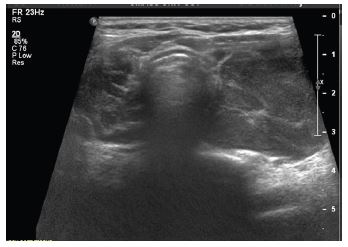

A 78-year-old female with a 10-year history of Hashimoto’s thyroiditis, biochemically on Levothyroxine 75 mcg daily presented to the endocrinology clinic with a 2-month symptom duration of unilateral left sided thyroid fullness and neck discomfort with asymmetric left thyroid enlargement confirmed on physical exam. An Ultrasound (US) of the thyroid and neck was significant for a unilateral increase in the size of the left thyroid lobe from 5.3×3.6×3.3 cm to 8.5×3.3×4.1 cm over 3 years and an enlarged left sided level 3 suspicious cervical lymph node measuring up to 1.4 cm in short axis, with loss of its fatty hilum (Figure 1).

Figure 1: Transverse view depicting newly enlarged left thyroid gland on ultrasound.